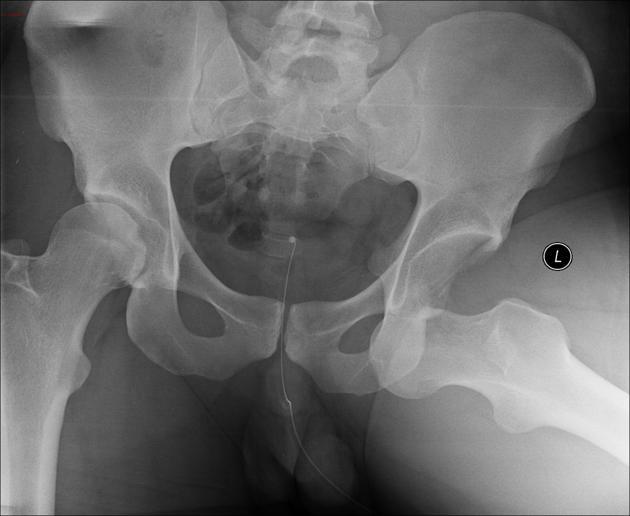

19. 고관절의 전방탈구와 후방탈구 중 어느 것이 더 흔한가?

고관절의 후방탈구가 더 흔하다. 대퇴골두의 상방 전위가 나타난다. 전방탈구에서는 대퇴골두가 전방과 내방으로 이동한다.

△ Posterior hip dislocation (이미지 출처 : http://radiopaedia.org/articles/hip-dislocation)

△ Anterior hip dislocation (이미지 출처 : http://radiopaedia.org/articles/hip-dislocation)